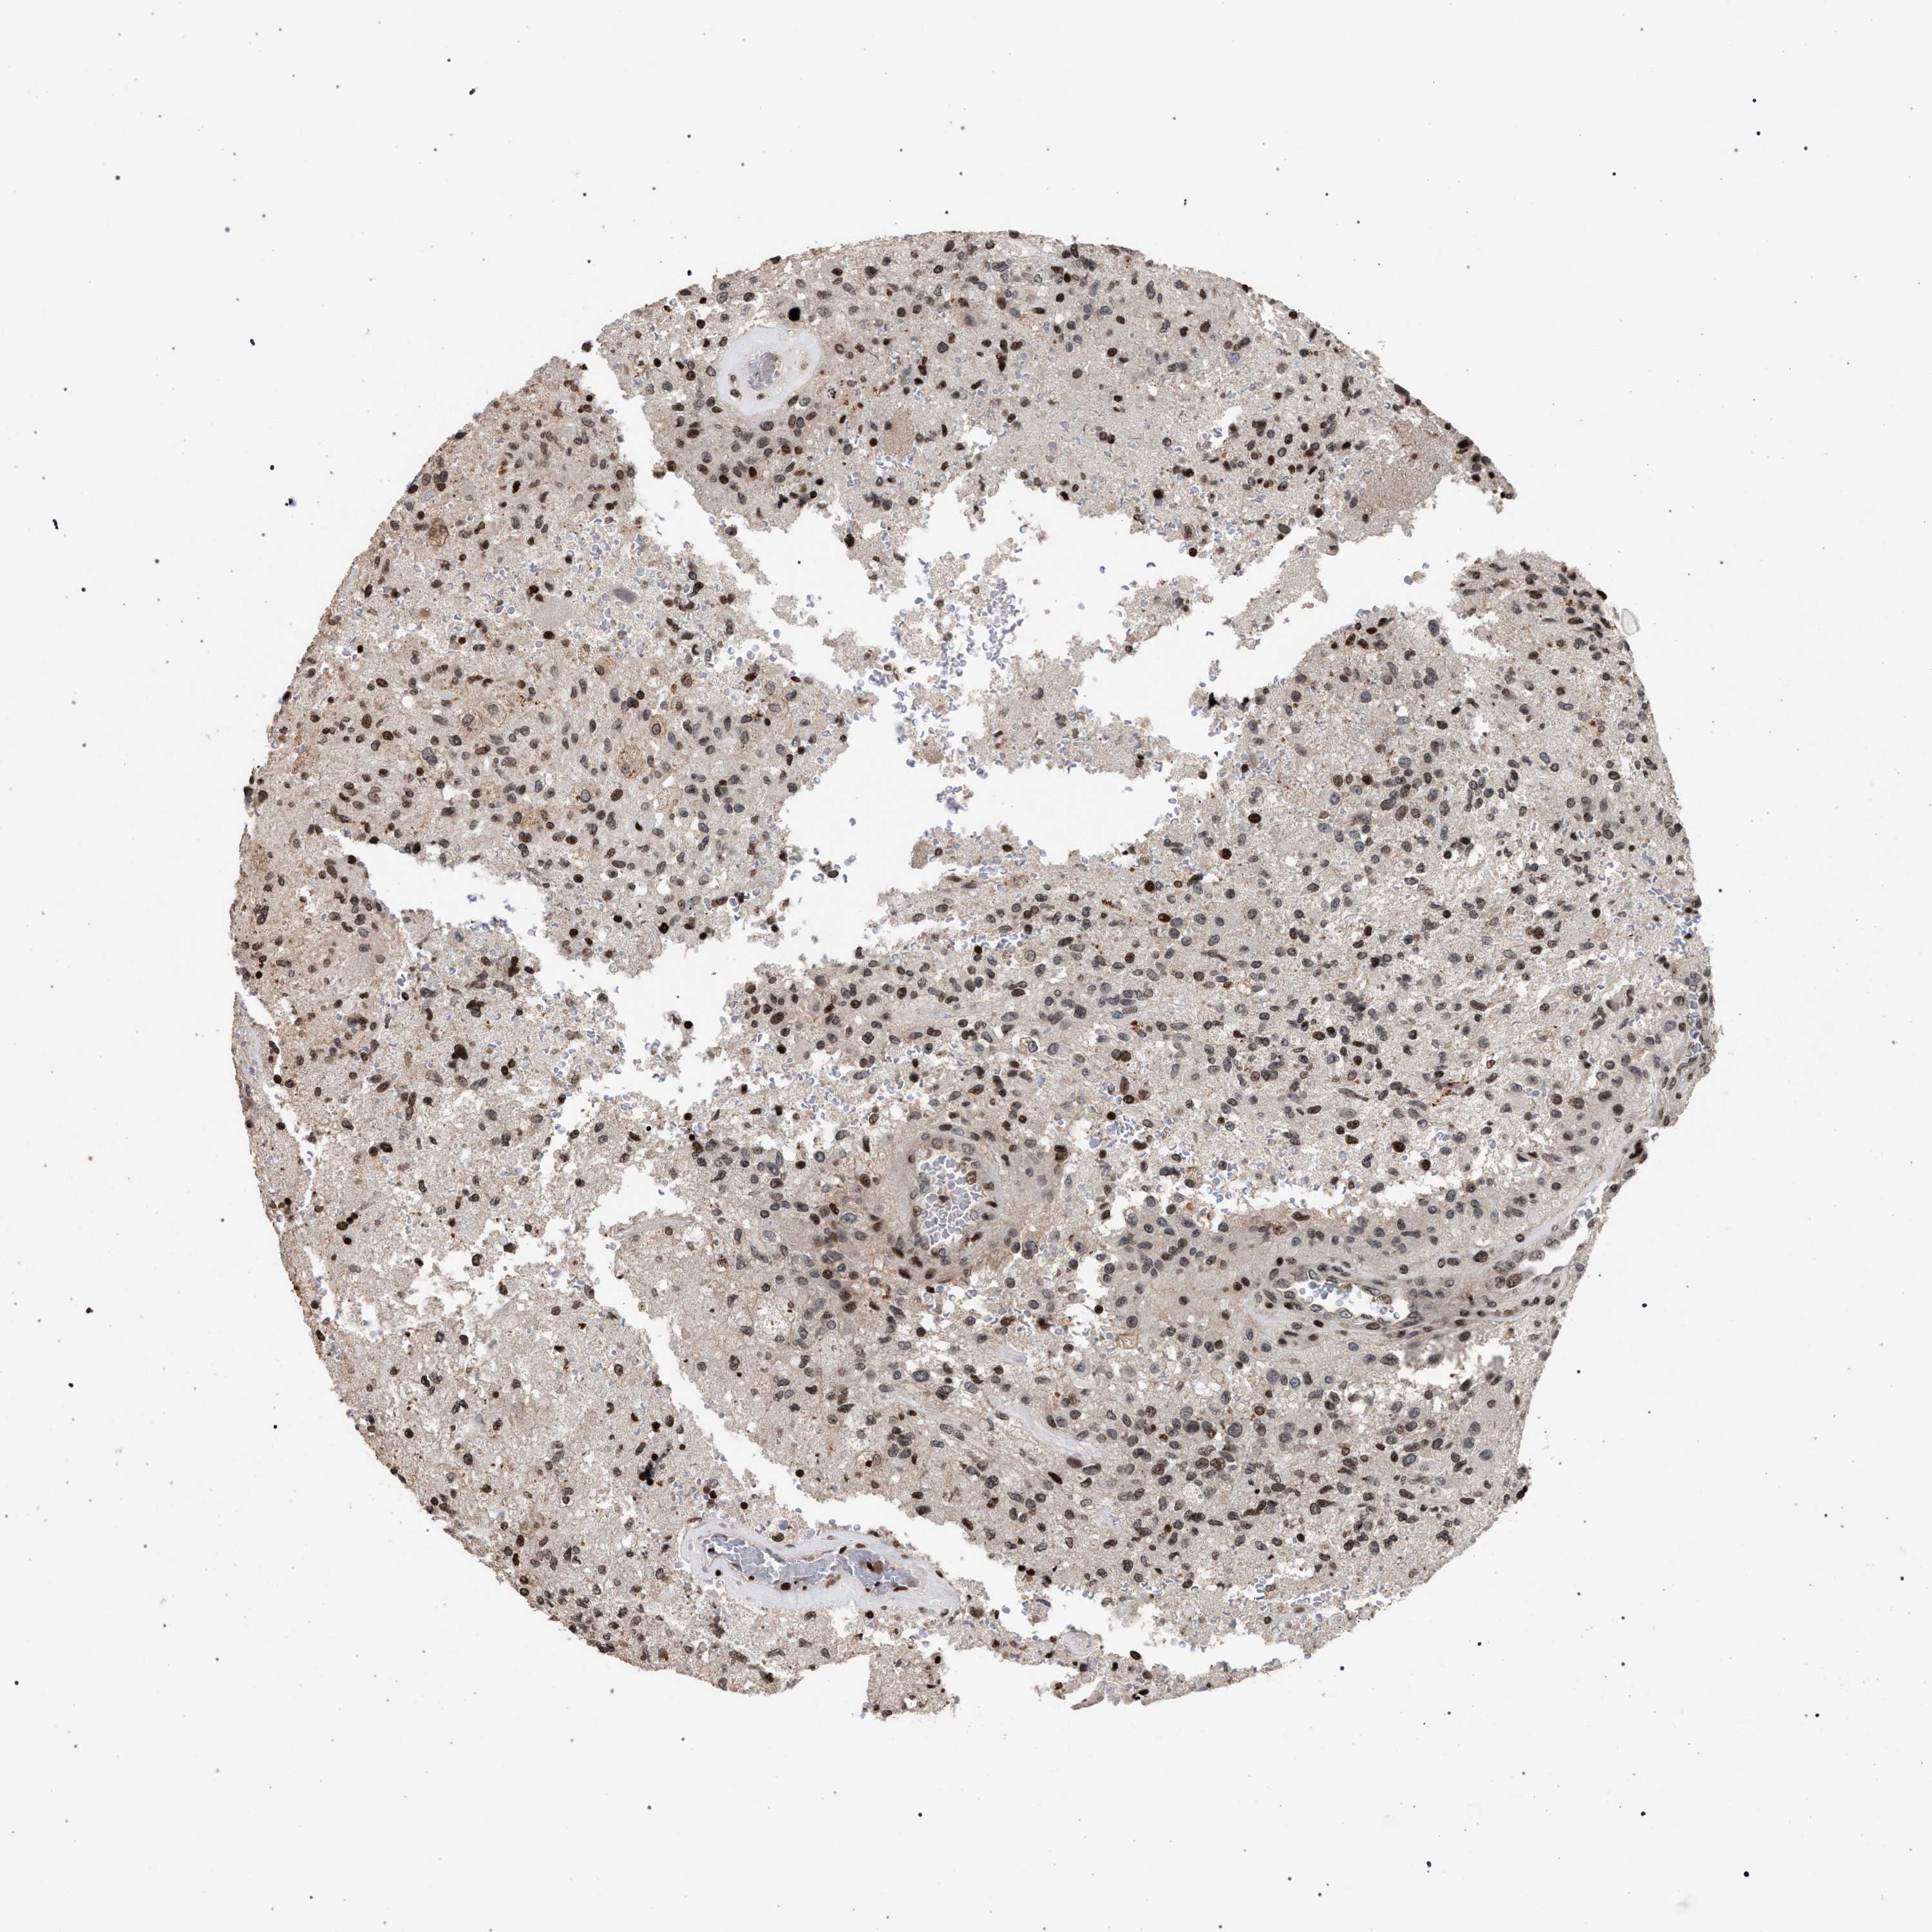

GLIOMA - Protein expressioni

A mouse-over function shows sample information and annotation data. Click on an image to view it in a full screen mode. Samples can be filtered based on level of antibody staining by selecting one or several of the following categories: high, medium, low and not detected. The assay and annotation is described here.

Note that samples used for immunohistochemistry by the Human Protein Atlas do not correspond to samples in the TCGA dataset.

Antibody stainingi

Antibody staining in the annotated cell types in the current human tissue is reported as not detected, low, medium, or high, based on conventional immunohistochemistry profiling in selected tissues. This score is based on the combination of the staining intensity and fraction of stained cells.

Each image is clickable and will lead to virtual microscopy that enables deeper exploration of all samples and also displays staining intensity scores, fraction scores and subcellular localization as well as patient and tissue information for each sample.

Antibody CAB022455

Staining

High

Medium

Low

Not detected

Intensity

Strong

Moderate

Weak

Negative

Quantity

>75%

75%-25%

<25%

None

Location

Nuclear

Cytoplasmic/membranous

Cytoplasmic/membranous,nuclear

Glioma, malignant, High grade

Glioma, malignant, Low grade